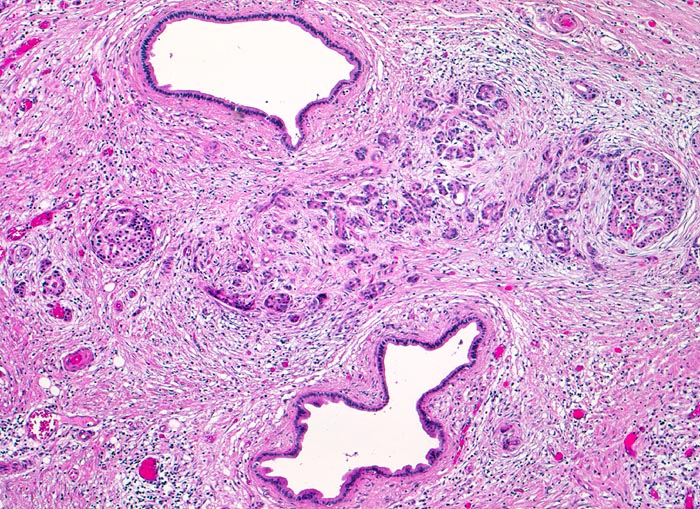

Zwischen zwei dilatierten Pankreasgängen ist ein stark fibrosiertes Pankreasläppchen mit atrophen Acini erkennbar. Daneben ist eine erhaltene Insel erkennbar. Das Parenchym ist stark fibrosiert. Die andeutungsweise erkennbare Läppchenarchitektur und die fehlenden Zellatypien helfen zur Abgrenzung des entzündlich veränderten atrophen Parenchyms von einem Tumorinfiltrat (ungeordnete Drüsenschläuche).

Unscharf begrenzter weisser derber Herd im Pankreaskopfbereich. Stenosierung und praestenotische Dilatation von Ductus choledochus und Pankreasgang vor der Papille.

Zunehmender schmerzloser Ikterus. Sonographische Darstellung einer 4cm grossen echoarmen Raumforderung im Pankreaskopfbereich. Dilatation des Pankreasganges und des Ductus choledochus. Whipple Operation.

Ursache einer obstruktiven Pankreatitis ist meist eine ausgeprägte Stenose des Hauptgangs, am häufigsten durch

einen Tumor im Pankreaskopf. Weniger

häufig sind große, nahe der Papille eingeklemmte Gallensteine. Durch den langzeitigen Gangverschluß kommt es zum Untergang aller stromaufwärts der Obstruktion liegenden Azinuszellen. Da es im Bereich der chronischen Pankreatitis und des Tumors (Desmoplasie) zu einer Fibrose kommt, ist es makroskopisch oft nicht möglich den Tumor von reaktiven Veränderungen abzugrenzen.